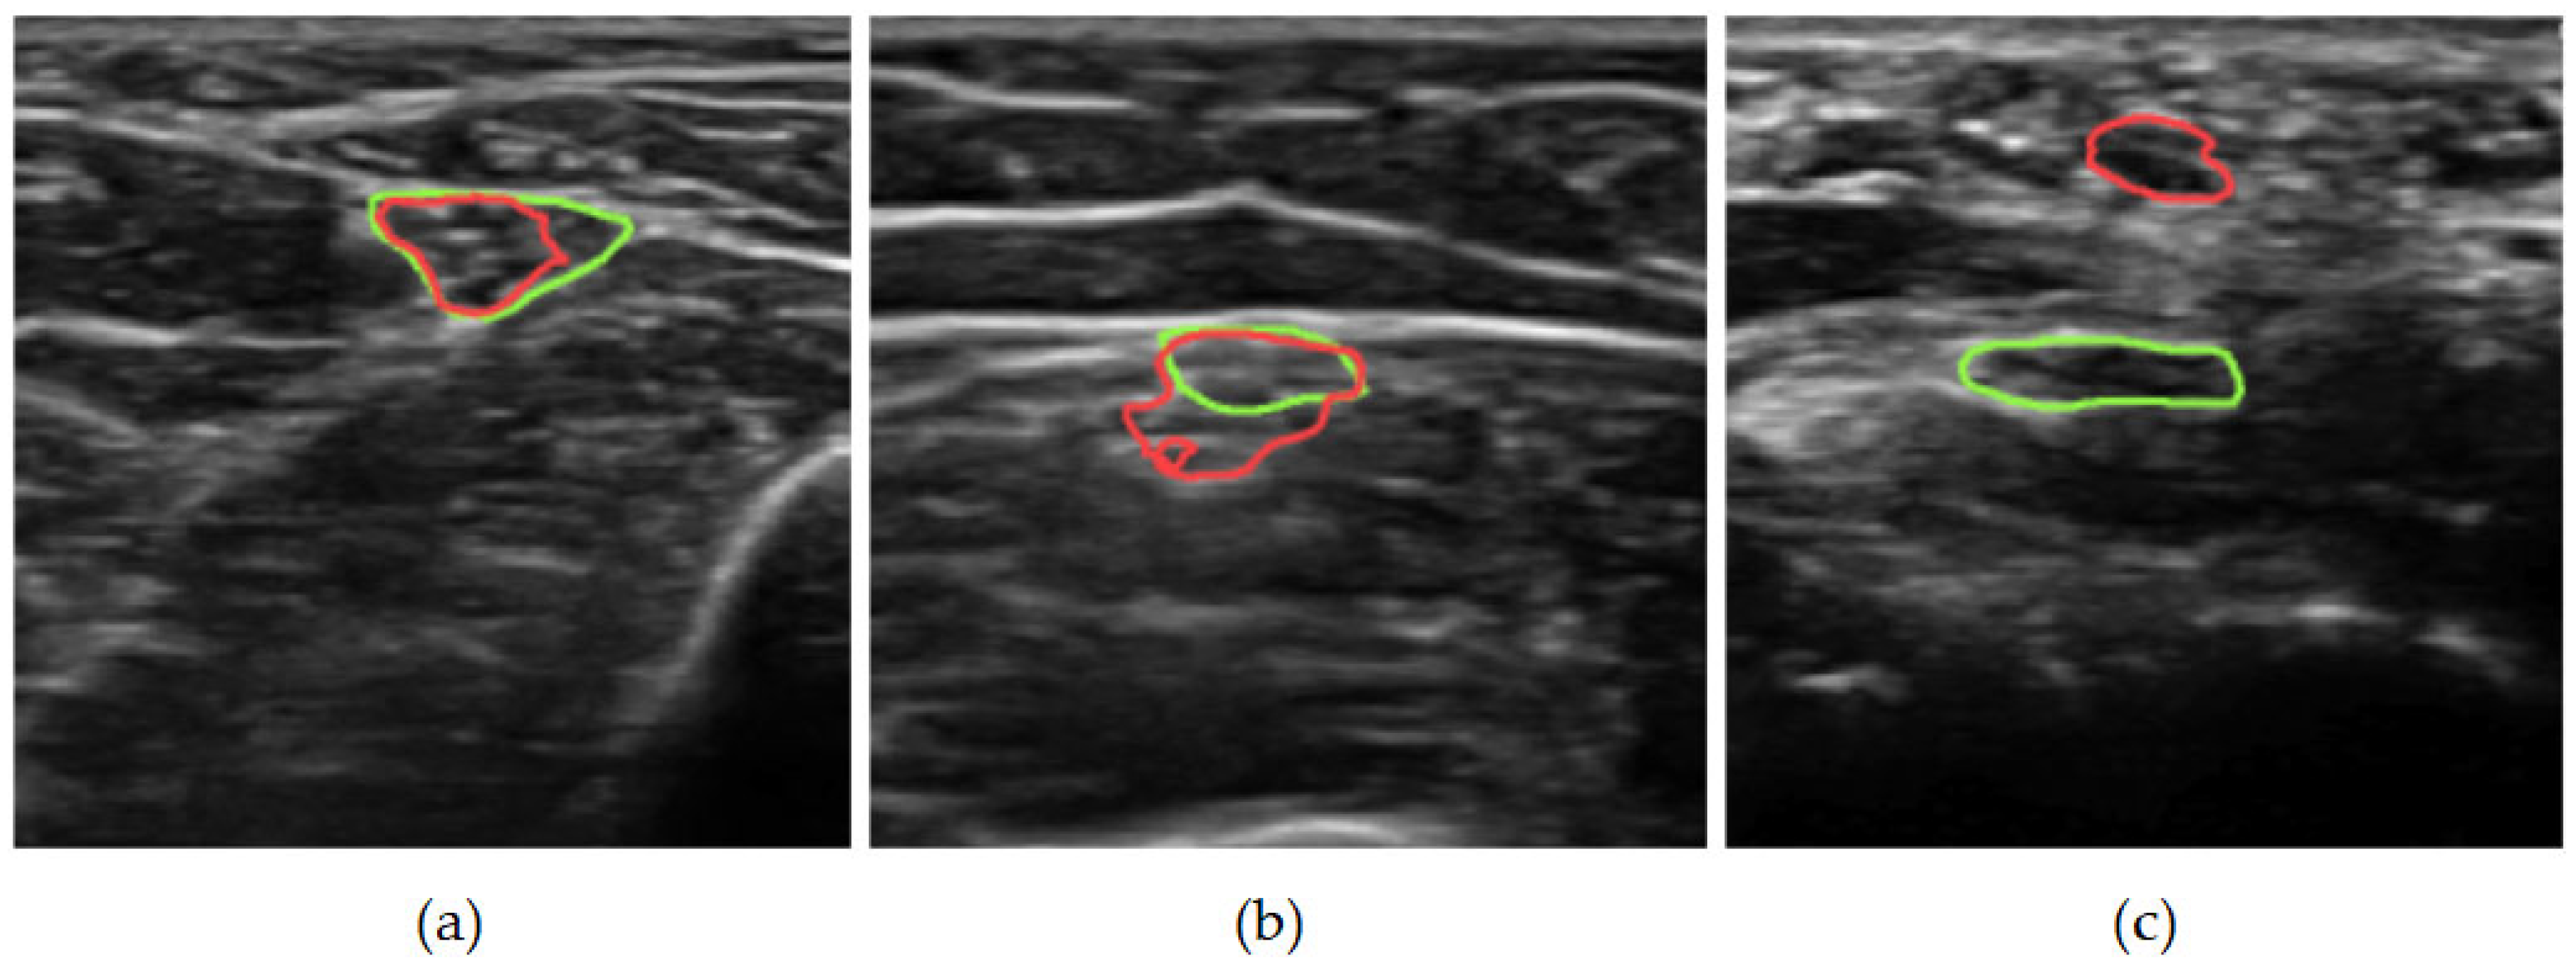

3.2. Qualitative